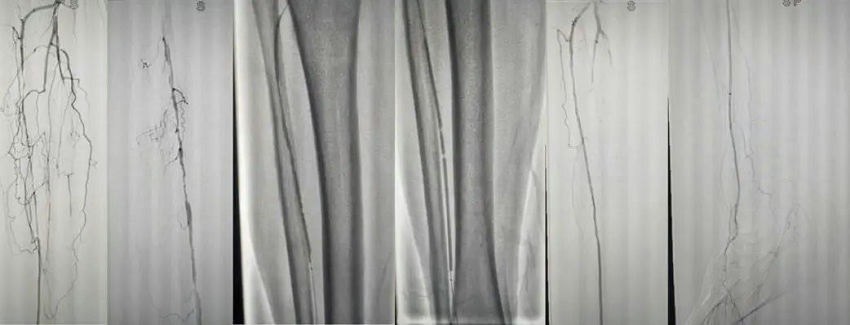

▲ 术中造影可见胫前动脉节段性重度狭窄,胫后动脉及腓动脉远端闭塞,手术开通胫前动脉并球囊扩张,复查造影,胫前动脉血流通畅,并通过足底弓代偿至足跟部。

经过血管外科专家团队会诊,考虑老先生为下肢血管闭塞,通过下肢动脉CTA检查,明确了其右腿血管膝关节以下多发闭塞,随即给予血管开通手术治疗,并对脚后跟溃烂部位进行切开清创,经过后期的持续性治疗,老先生的溃烂部位得以愈合。